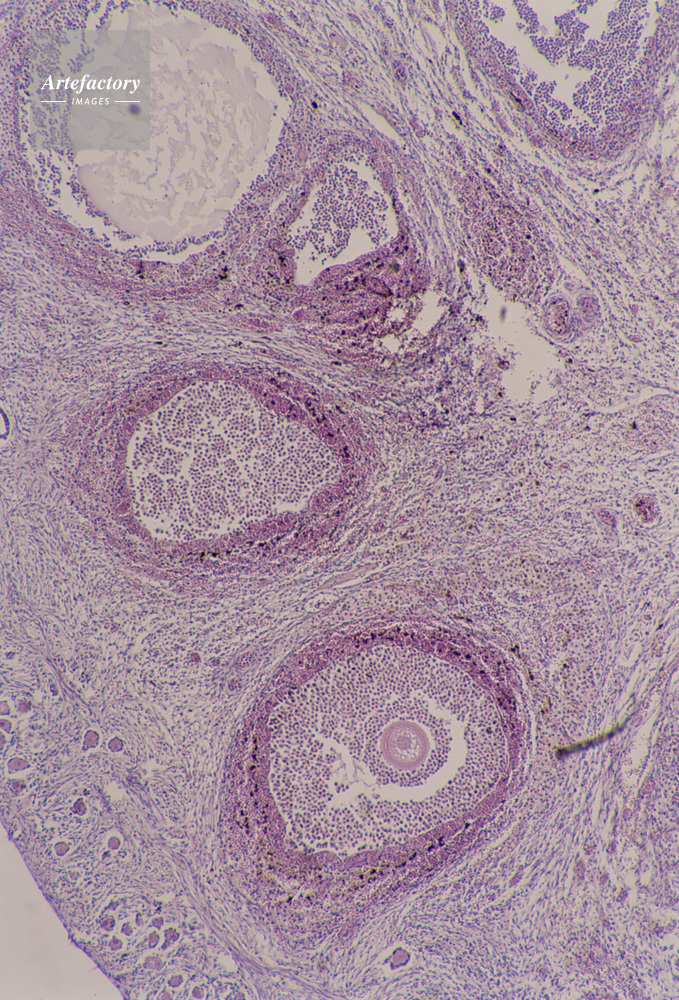

| キャプション | 卵巣,40倍,卵巣組織 | 制限事項 | ||

| ソース | ピクセル数 | 3772px × 5556px | ||

| 撮影地 | 印刷サイズ | 20.6cm × 30.3cm | ||